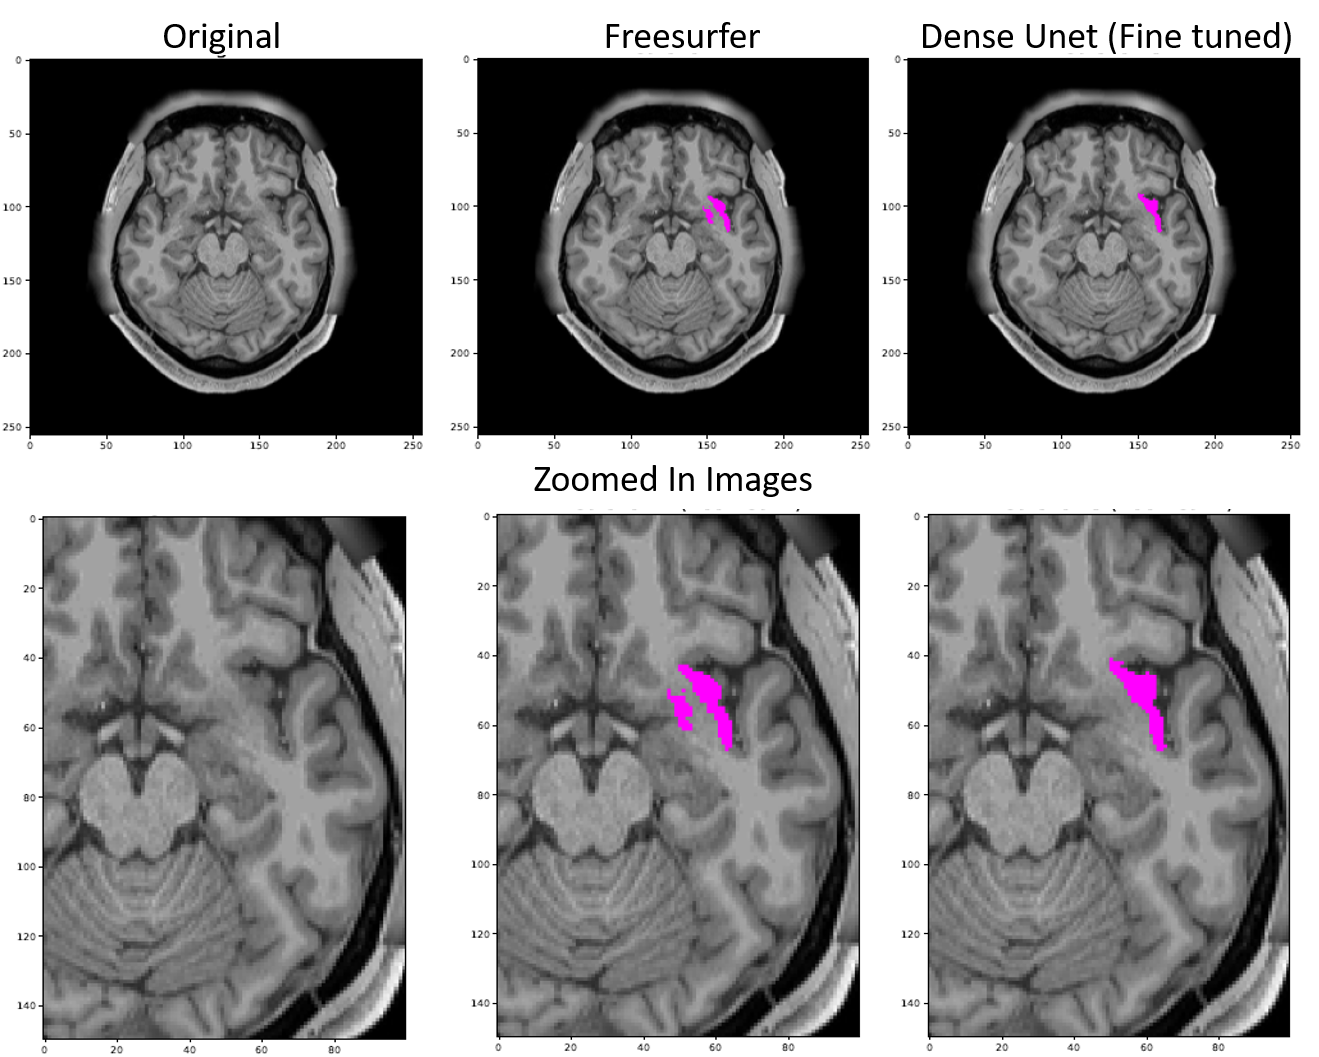

Three expert readers performed visual inspection and assessment of the segmentation results. There were two attending neuroradiologists with 3 and 5 years of experience and one second-year radiology resident. Each reader was asked to rate 40 different predictions for each ROI (20 in each brain hemisphere) such as shown in figure 2. Readers were blinded to the algorithm used to predict the segmentation and examples were presented in a randomized order. Each prediction presented consisted of a single slice containing a minimum of 40 pixels within the ROI, ensuring that enough of the structure being assessed was present on the given image. A sample slice rated by the readers is shown in figure 2.

Figure 2: A sample segmentation of Right Insula used in the expert reader evaluation. Here, predictions 1, 2 and 3 are from the Finetuned model, Freesurfer, and non-Finetuned model respectively; though in the reader study, numbering and order of presentation of the predictions are randomized and a total of 280 of examples are presented. Each reader is asked to rate each example for the quality of segmentation on a 5-point Likert-type scale.